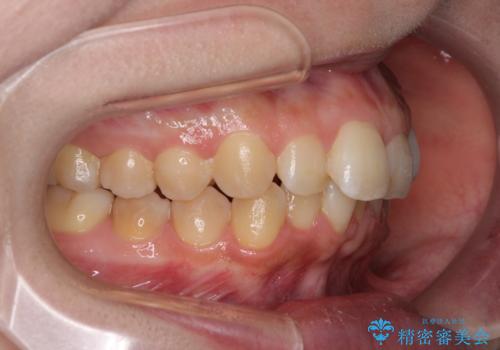

前歯のデコボコをインビザライン矯正で綺麗に改善

- 上下前歯のデコボコを気にして来院された患者様です。

全体的に叢生は軽度であったため、インビザラインにて矯正治療を行うこととしました。

舌の突出癖改善がうまくいかず、途中で舌小帯の切除を行いました。

気になる段差を納得いくまで改善させたため、治療期間は長くなりましたが、綺麗な仕上がりとなりました。